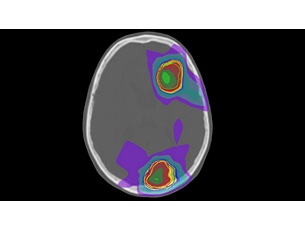

Whether for external beam radiation therapy (RT) or brachytherapy, integrating MR imaging into CT‑based planning can harness the power of MRI and transform patient management. With MRI’s excellent soft-tissue contrast, you can clearly see the tumor and organs at risk. So you can support accuracy in delineation and design the best possible treatment plans. Image courtesy of William Beaumont Health System, Detroit, USA - A superb MRI platform for radiation oncology

See clearly in treatment planning

Enjoy consistent, excellent image quality for multiple anatomies. Versatile arrangements of dStream coils work together with ExamCards tailored for RT to provide high-contrast images with high geometric fidelity. Quickly execute complete imaging protocols for prostate, female pelvis, brain, head and neck, and spine. - Learn and share MRI expertise

Whether for external beam radiation therapy (RT) or brachytherapy, integrating MR imaging into CT‑based planning can harness the power of MRI and transform patient management. With MRI’s excellent soft-tissue contrast, you can clearly see the tumor and organs at risk. So you can support accuracy in delineation and design the best possible treatment plans. Image courtesy of William Beaumont Health System, Detroit, USA - A superb MRI platform for radiation oncology

See clearly in treatment planning

Enjoy consistent, excellent image quality for multiple anatomies. Versatile arrangements of dStream coils work together with ExamCards tailored for RT to provide high-contrast images with high geometric fidelity. Quickly execute complete imaging protocols for prostate, female pelvis, brain, head and neck, and spine. - Learn and share MRI expertise